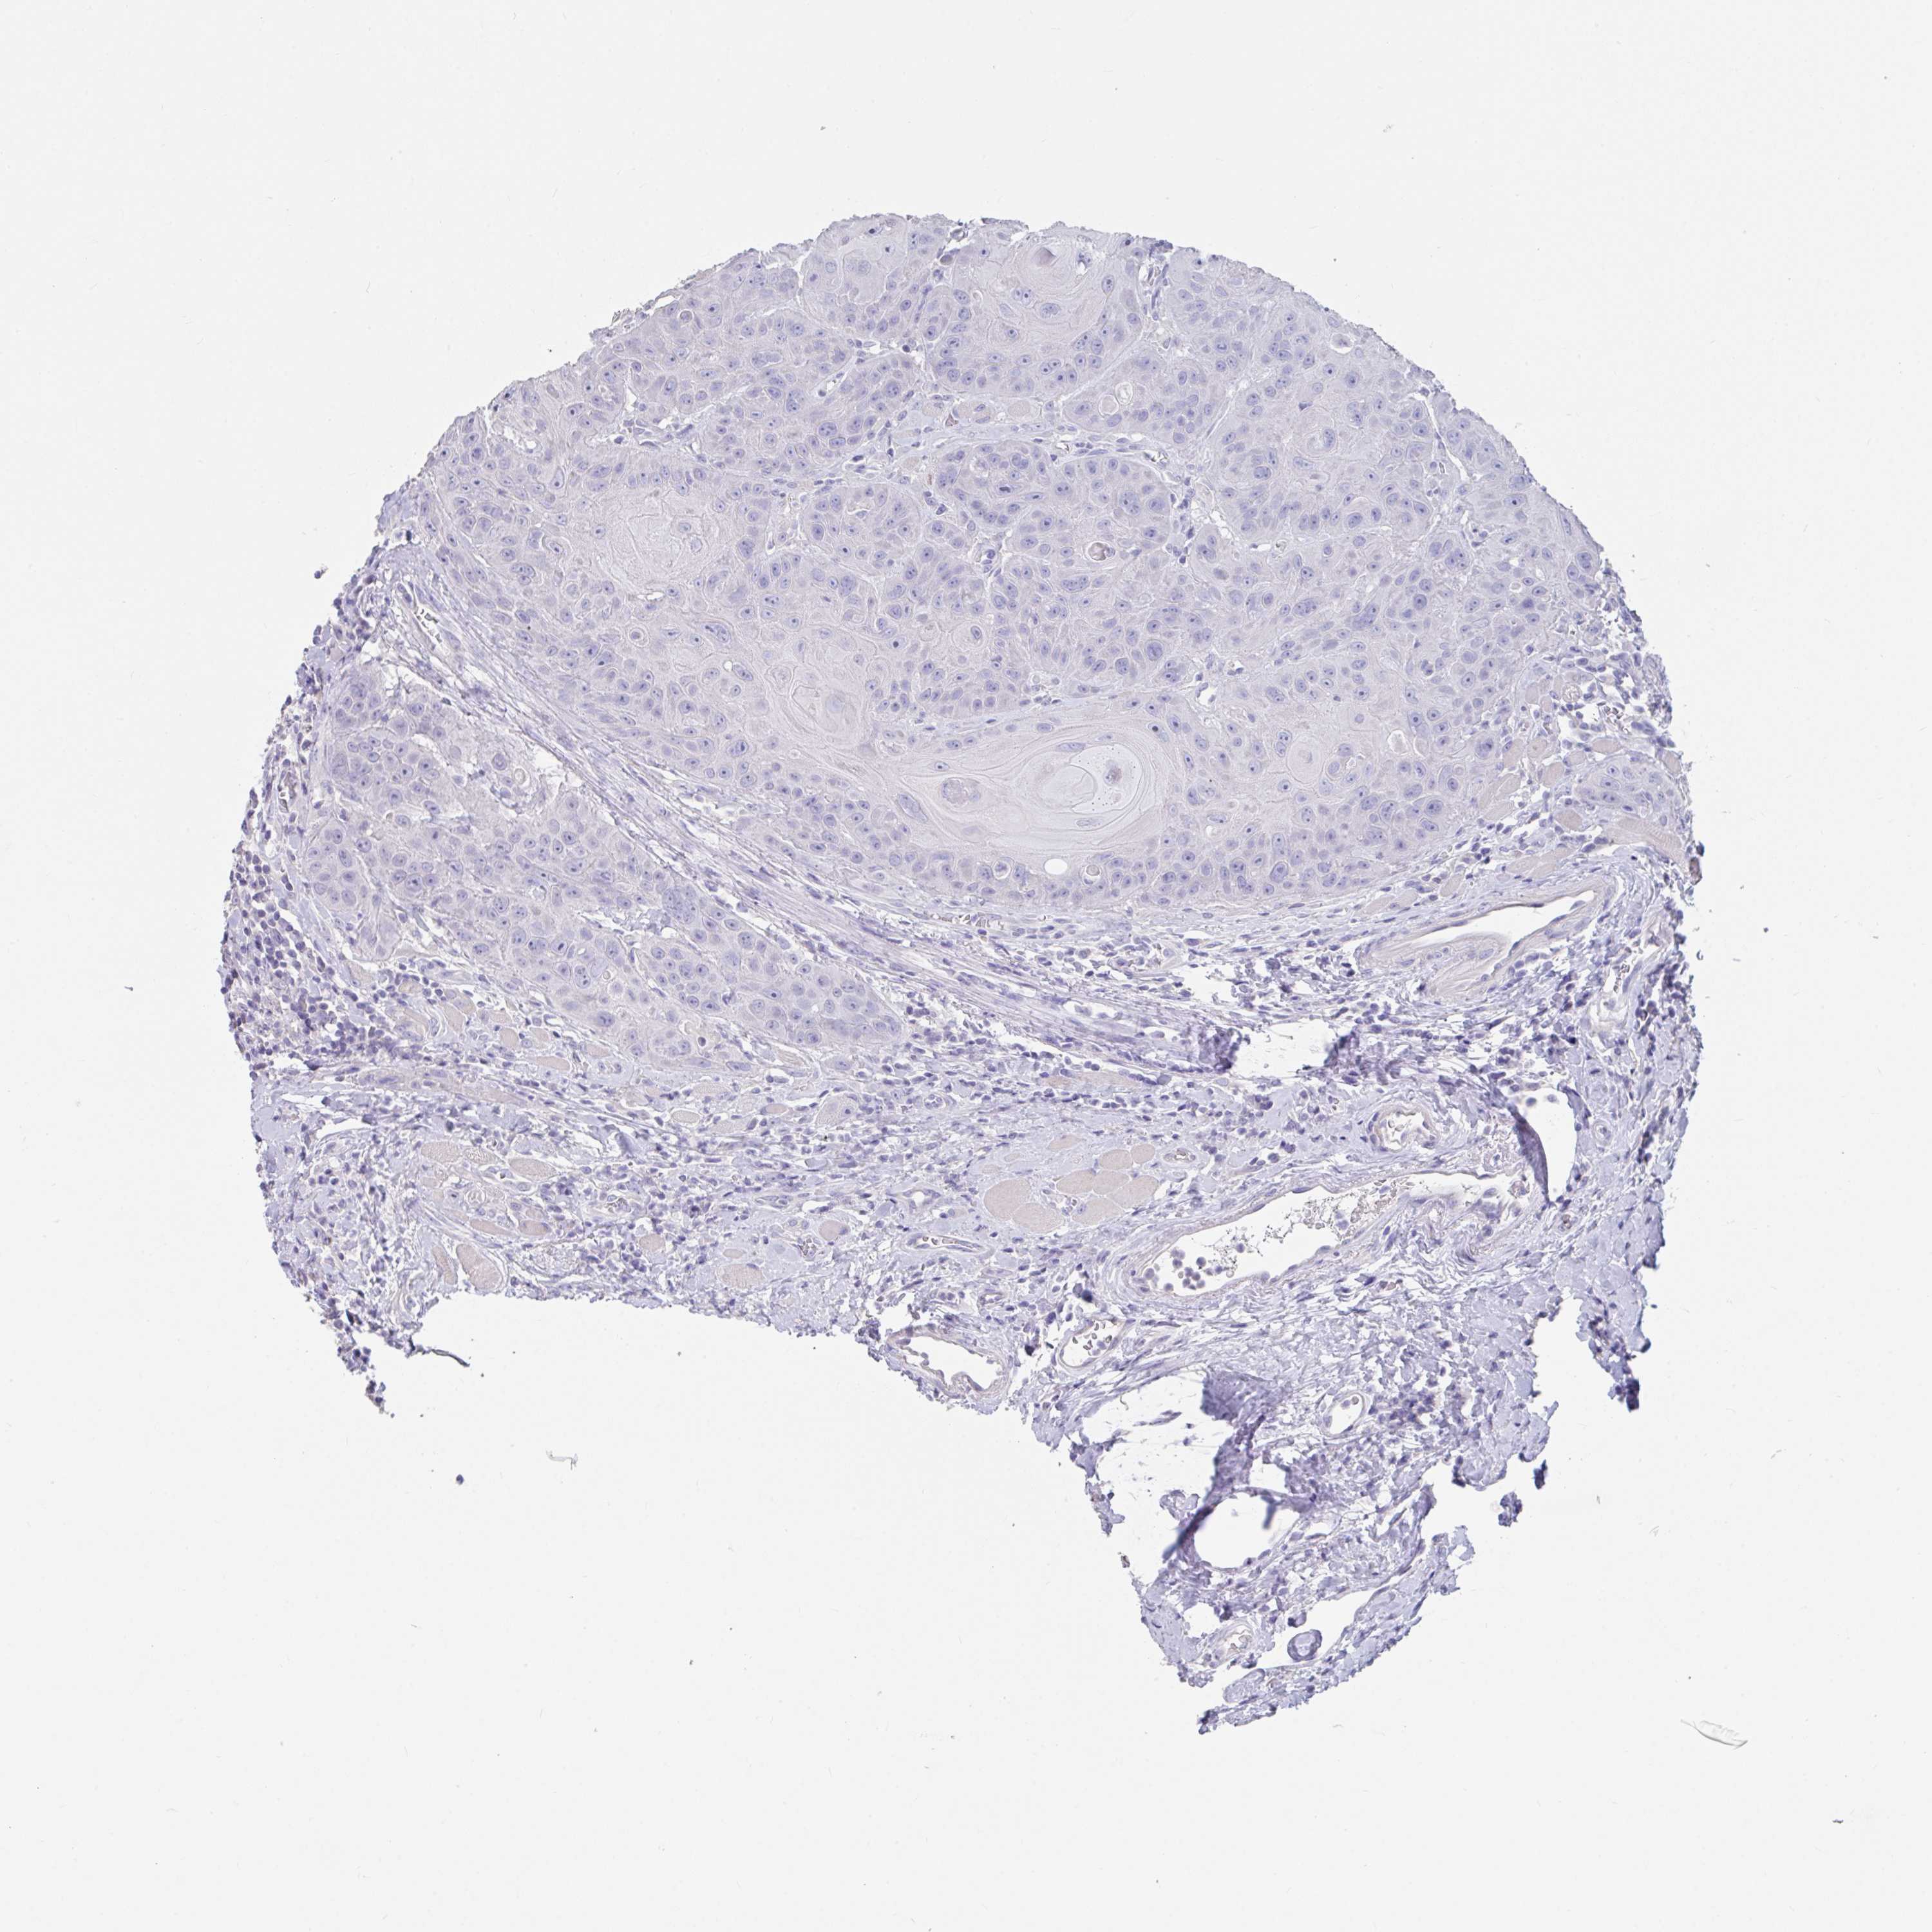

HEAD AND NECK CANCER - Protein expressioni

A mouse-over function shows sample information and annotation data. Click on an image to view it in a full screen mode. Samples can be filtered based on level of antibody staining by selecting one or several of the following categories: high, medium, low and not detected. The assay and annotation is described here.

Antibody stainingi

Antibody staining in the annotated cell types in the current human tissue is reported as not detected, low, medium, or high, based on conventional immunohistochemistry profiling in selected tissues. This score is based on the combination of the staining intensity and fraction of stained cells.

Each image is clickable and will lead to virtual microscopy that enables deeper exploration of all samples and also displays staining intensity scores, fraction scores and subcellular localization as well as patient and tissue information for each sample.

Antibody HPA046977

Antibody HPA054176

Staining

Squamous cell carcinoma, NOS